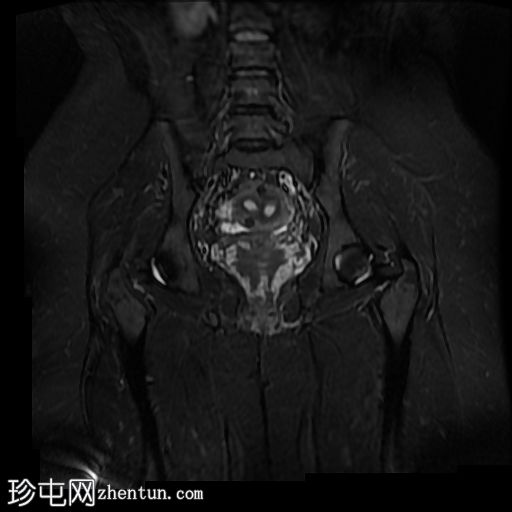

冠状位(沿子宫矢状轴的SFOV)T2

STIR

偶然发现子宫纵隔,子宫角间夹角为51度,纵隔长度为19mm。

子宫底部可见少量壁内及浆膜下肌瘤。